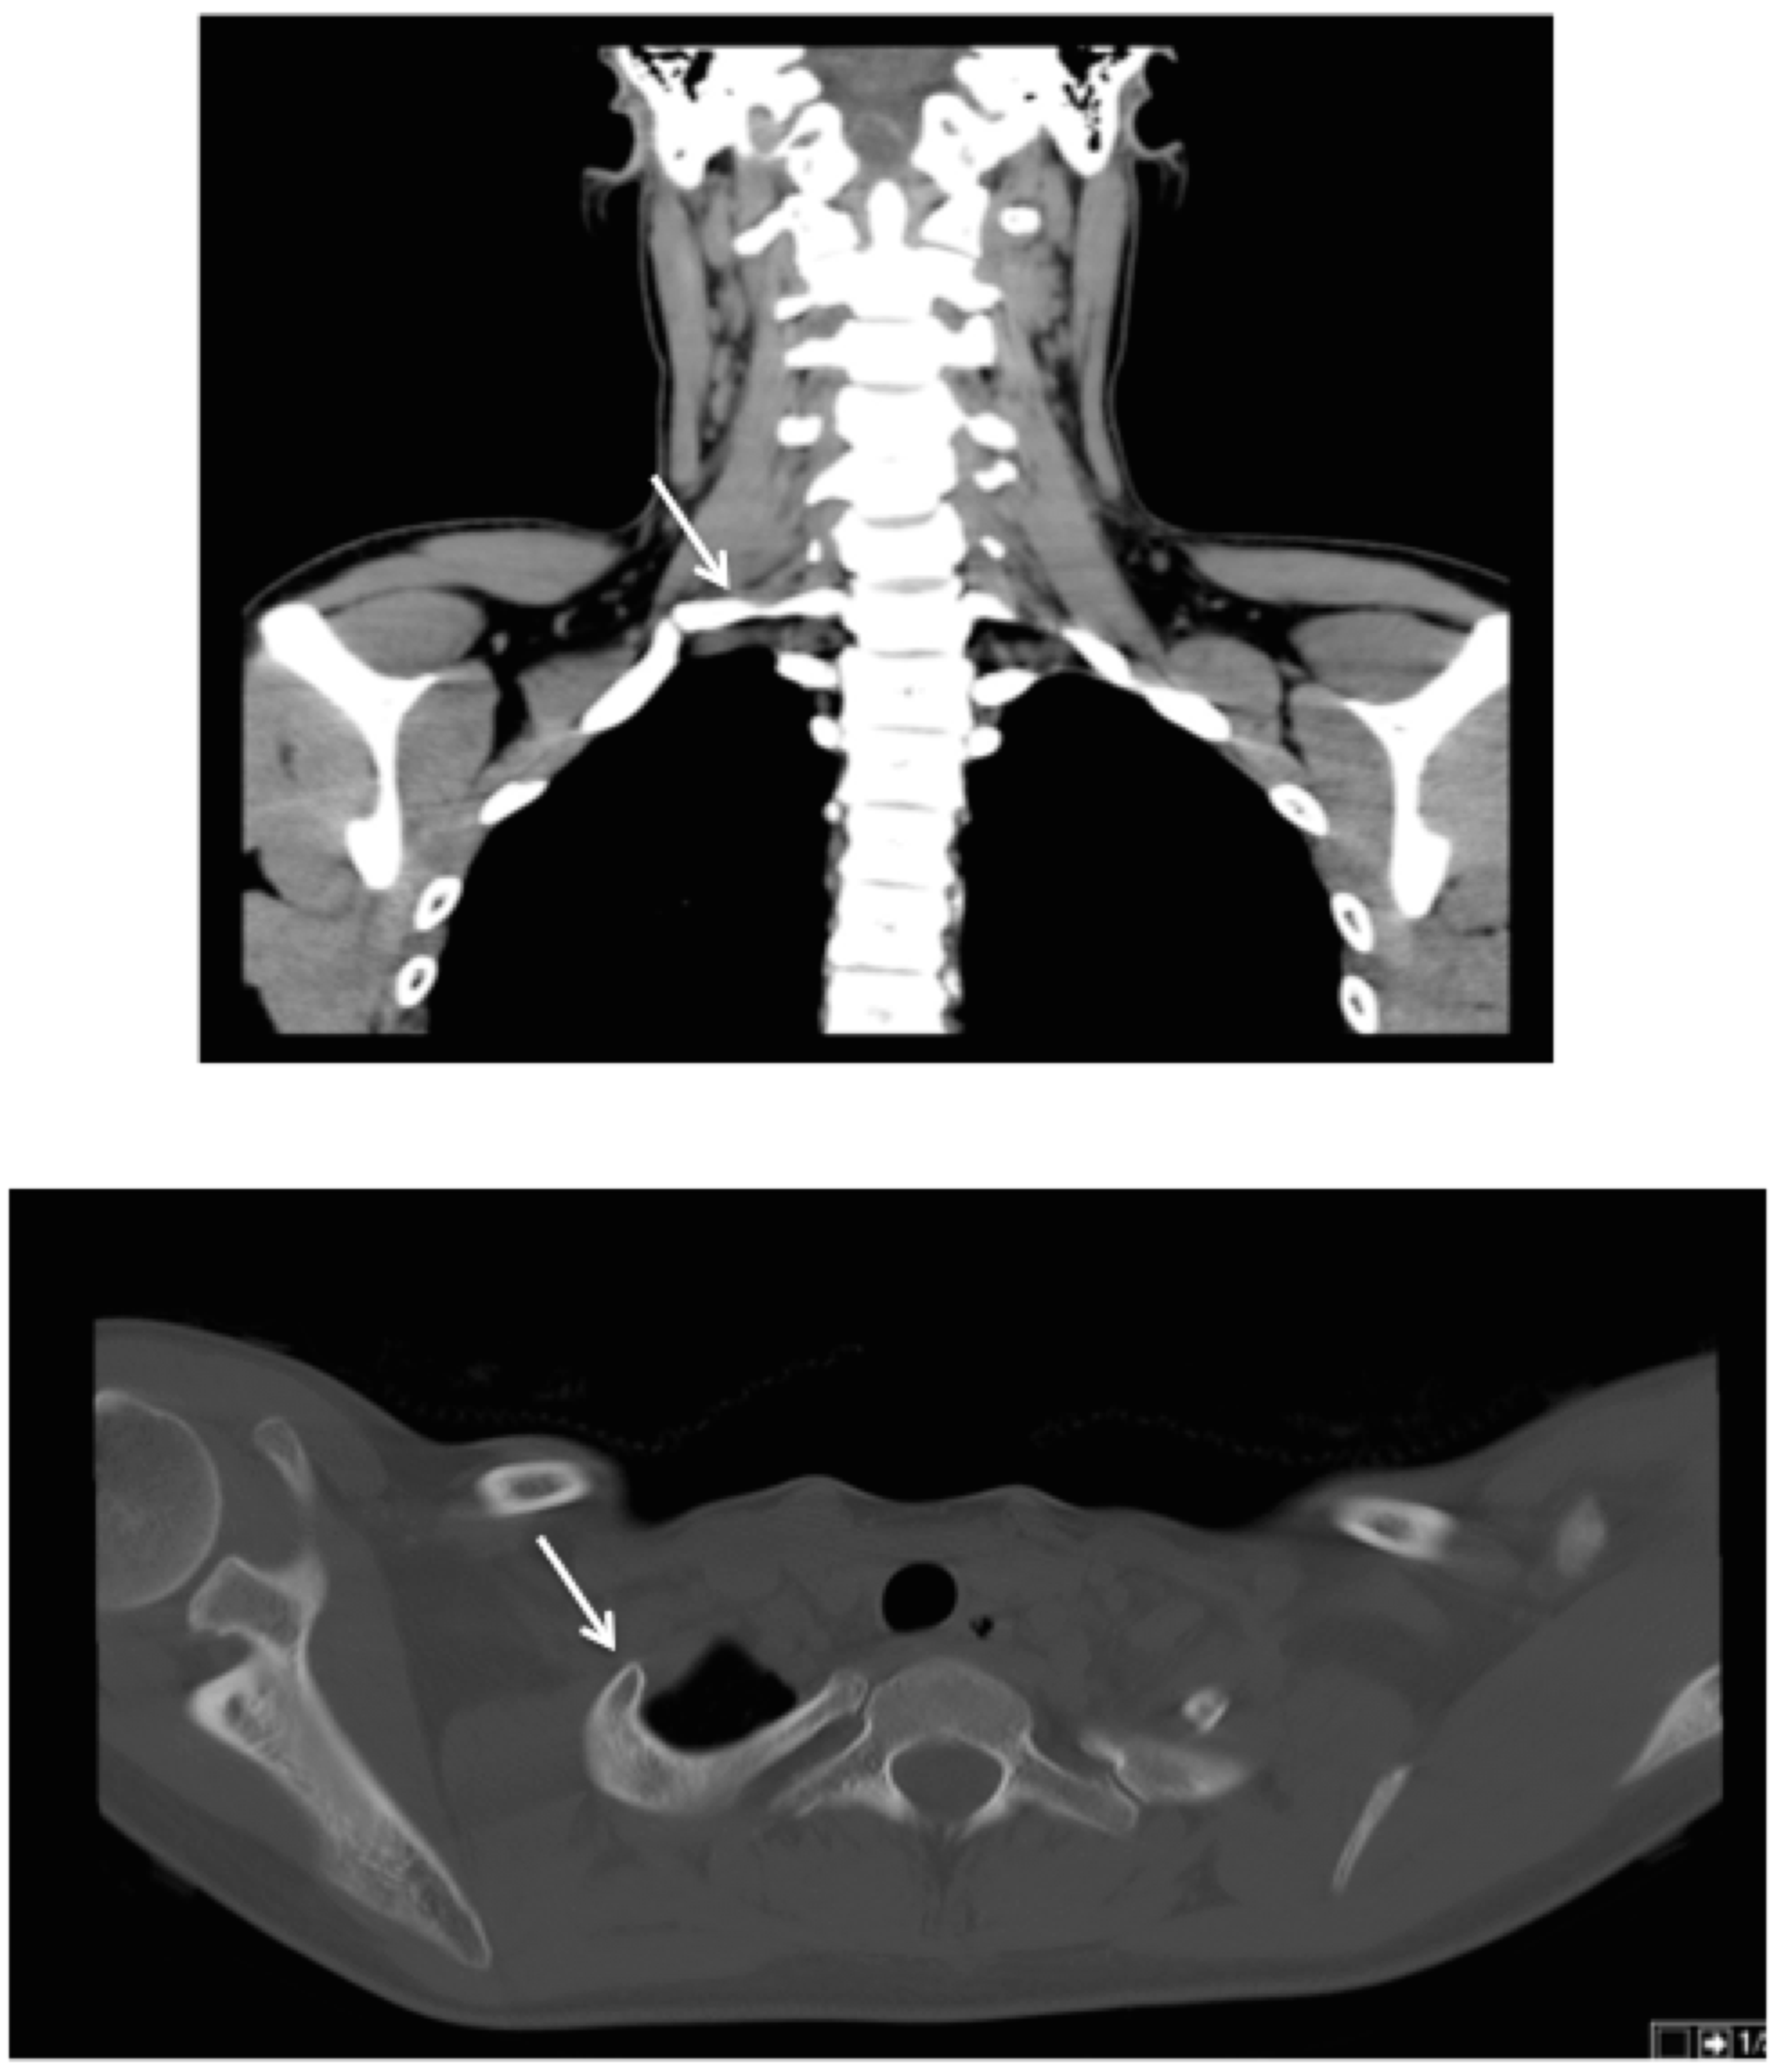

Electromyography revealed a reduction in the sensitivity responses of the right medial antebrachial cutaneous and ulnar nerves, a reduced number of F responses of the right median nerve, and an increased latency of the F responses of the right ulnar nerve. No changes were found on the sensitive or motor conduction on the left side. The computed tomography scan showed the presence of cervical ribs on C7, larger on the right side, which articulated with the top of the first costal arch (Figure 2).

Figure 2. Computed tomography scan showing the C7 cervical ribs (arrows), larger on the right side, with an initial segment with a posterolateral orientation and a distal segment with a anterolateral orientation, which articulates with the top of the first costal arch. Upper image: coronal view; lower image: axial view.